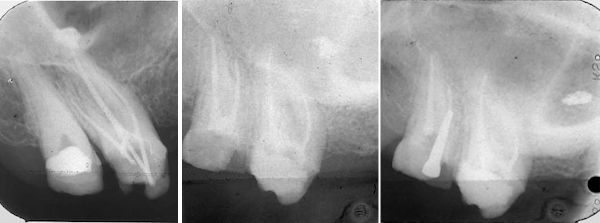

37-jährige Patientin (13.02.1986 / 404)

Das überfüllte AH26 ist ganz verschwunden, und die Patientin hat keine Schmerzen in der Kieferhöhle bekommen.

73-jährige Patientin (18.06.2021 / 404)

35 Jahre nach der Wurzelbehandlung sind starke Kieferhöhlenschmerzen entstanden. Das Röntgenbild vom Zahn 16 sieht gut aus. Um sicher zu sein wird noch ein DVT hergestellt.